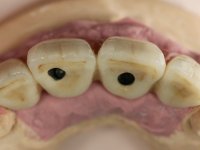

Segunda Fase

6 meses após a colocação da ponte, o paciente sofre um novo traumatismo comprometendo a viabilidade dos dentes 1.2 e 1.1. Foi realizada uma prótese removível acrílica para reabilitar provisoriamente o paciente enquanto foram extraídos os dentes 1.2 e 1.1 e foi colocado o implante no local do dente 1.1. Passados 3 meses foi realizada uma impressão ao implante colocado no 1.1 e simultaneamente foi feito um arrasto da ponte dos dentes 2.1 e 2.2. Para esse efeito no implante 2.1 foi utilizado um parafuso de uma peça de transferência. Dessa forma conseguiu-se impressionar corretamente a arquitetura gengival do sector antero-superior. O objetivo era simultaneamente impressionar corretamente esta zona e aproveitar a estrutura metálica desta ponte para confecionar a nova ponte de 4 elementos. Foi colocado um parafuso de cicatrização no implante 2.1 e foram acrescentados os dentes 2.1 e 2.2 na prótese removível. Com perícia laboratorial foi criada uma nova infraestrutura metálica de 4 elementos assente nos implantes 1.1 e 2.1 e com os elementos pônticos suspensos 1.2 e 2.2. No implante 2.1 manteve-se a conexão interna ao implante no implante 1.1 optou-se por uma peça intermédia facilitando a inserção da infraestrutura. A nova infraestrutura foi verificada em boca. Como pode ter havido alguma alteração da arquitetura gengival com a remoção da ponte e colocação do parafuso de cicatrização no 2.1, foi feita uma chave de silicone para permitir uma impressão de arrasto da infraestrutura metálica. Uma nova gengiva artificial foi realizada no modelo de trabalho de acordo com esta impressão de arrasto. Foi colocada cerâmica de tonalidade coronária e gengival. A peça protética foi aparafusada lentamente em boca para permitir uma adaptação dos tecidos moles. Após o correto assentamento e verificação imagiológica a ponte foi definitivamente apertada em boca e os orifícios de acesso obturados. Independentemente dos infortúnios que o paciente teve, pude ter a satisfação de o ver contente com esta reabilitação.